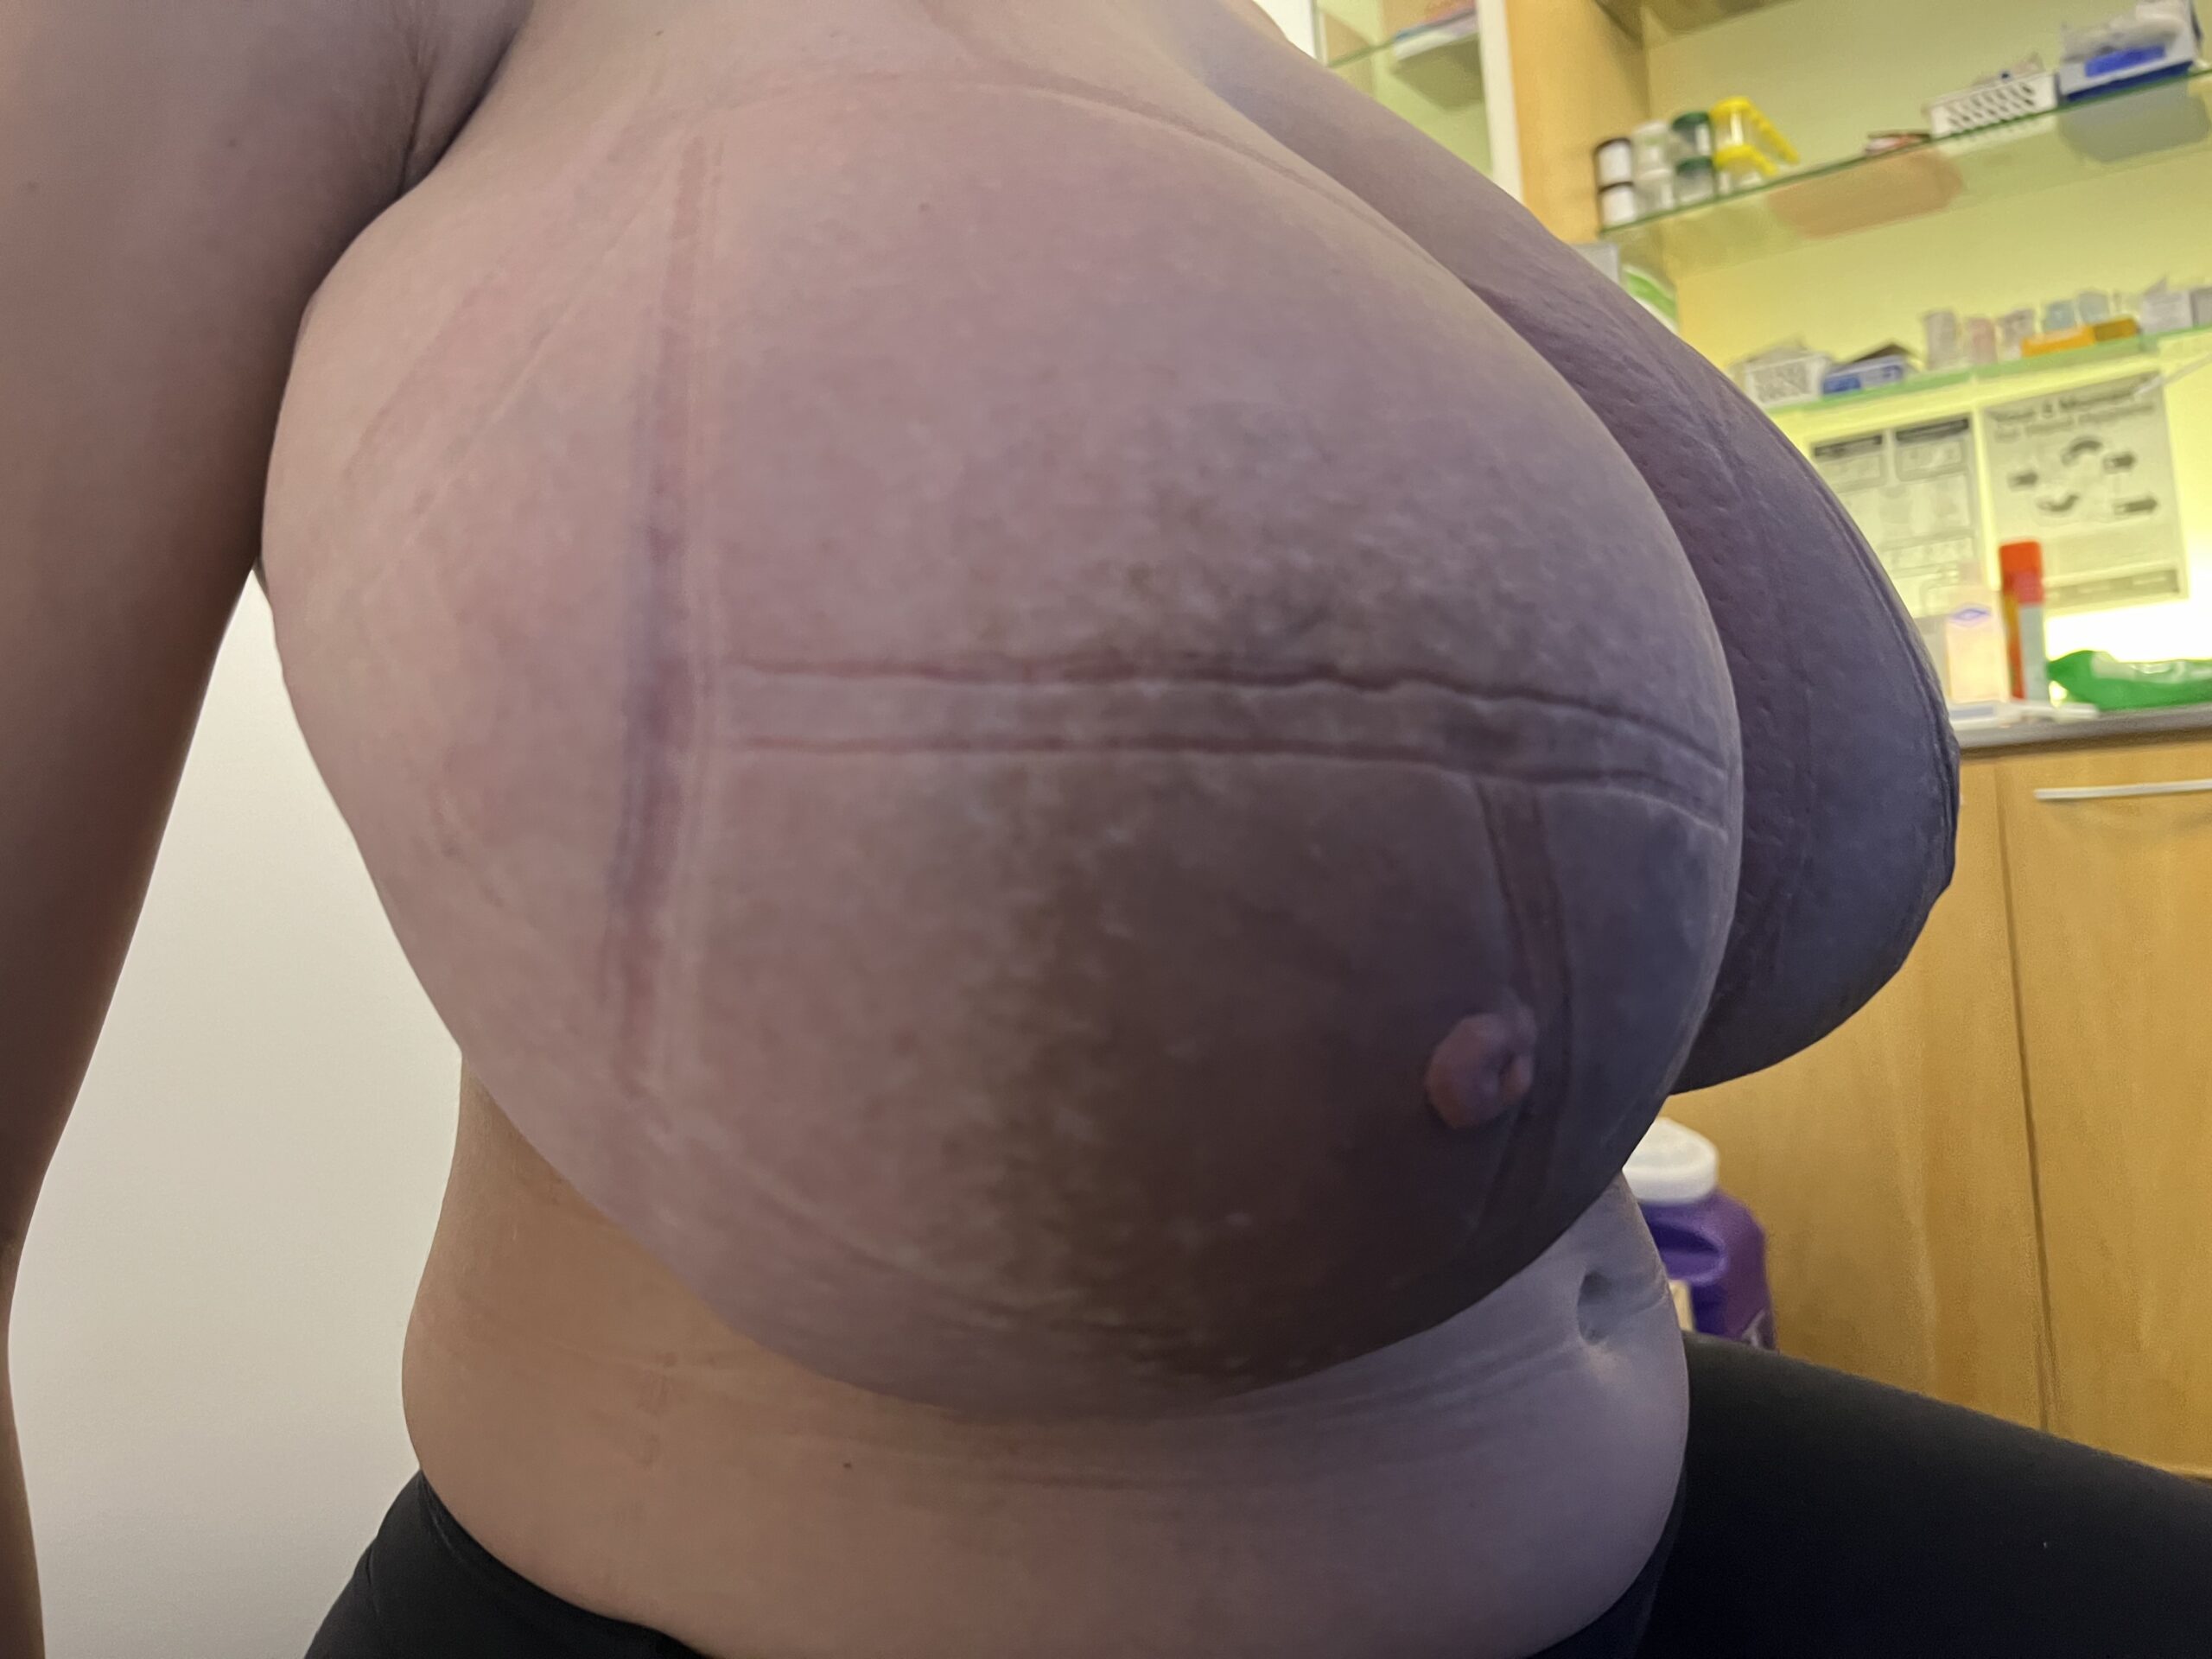

Gigantomastia

Gestational gigantomastia likely represents a spectrum of excessive breast growth during pregnancy. It may include women who grow multiple cup sizes, or those for whom the breast growth is so significant it can cause mobility impairments. Hormonal factors may play a role in gigantomastia, but true cause remains unknown. It also remains unclear whether the growth represents true glandular development or simply fluid retention in the breast as occurs in other parts of the body during pregnancy. Women gigantomastia that is not significant enough to cause skin breakdown but do experience growth do not necessarily produce large volumes of milk.

Photo: Clara Farley

Photo: Clara Farley

Photo: Clara Farley

Photo: Clara Farley

During pregnancy, it is treated by bromocriptine (an anti-prolactin agent) alternating with metformin (modulates insulin). Postpartum, patients should be given bromocriptine or cabergoline (anti-prolactin agent) before lactogenesis II (secretory activation, or “milk coming in”) to reduce the risk of skin necrosis (ulceration and death of skin). Donor milk or formula supplementation should be planned. Patients can later undergo elective breast reduction. The patient above is pictured below at end of pregnancy after being treated with lymphatic drainage and bromocriptine during pregnancy:

Improvement in lymphedema with lymphatic drainage and supportive bra/garment, just before delivery. Photo: Clara Farley, MD